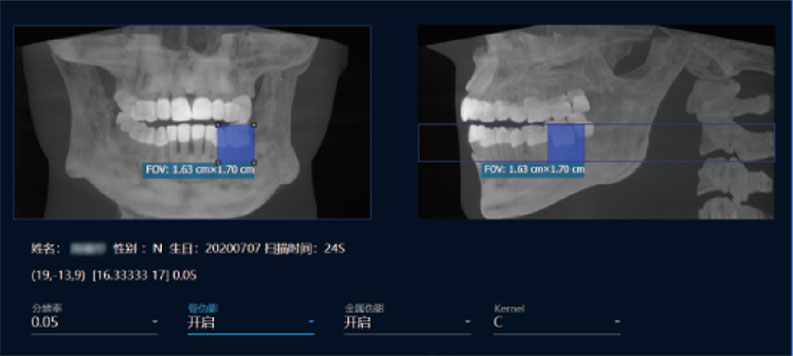

采用高性能CMOS探测器,最大FOV可达16x9cm星垂视野并支持无极可调,最小体素0.05mm。头颅采集模式,支持3s超快速扫描,最小像素99um,保证优质影像快速采集。

局部超清显示、 移动视野摄片

真人正侧位投影,实现CT成像区域无极可调

可根据临床需求任意调整成像区域大小实现局部超清三维显示

临床样片